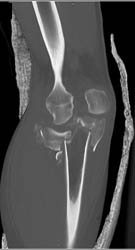

Tibial Plateau Fracture